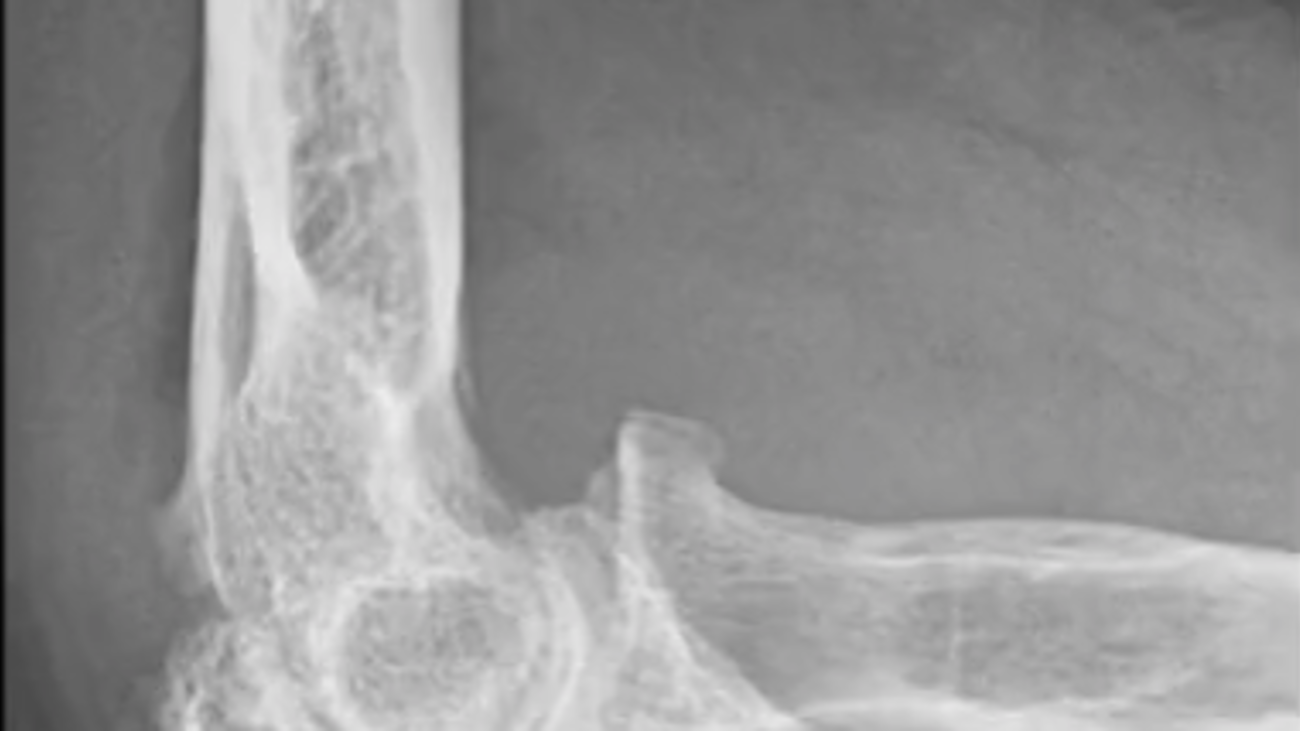

Arthroscopic Elbow Osteocapsular Arthroplasty Arthroscopy Techniques What Is A Elbow Arthroplasty elbow replacement is also called elbow arthroplasty or elbow joint replacement. elbow replacement surgery (sometimes referred to as total elbow arthroplasty) is an operation that surgeons. In total elbow replacement surgery, the damaged parts of the humerus and ulna are replaced with artificial components. The stems fit inside the hollow part of the bone called the canal. . What Is A Elbow Arthroplasty.